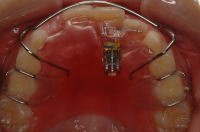

床矯正治療

![]() ① |

![]() ② |

![]() ③ |

![]() ④ |

この症例を含め、歯並びに何か異常を感じたらすぐに処置を行うことが大切です。

この症例は矯正開始(添付写真1)4ヶ月で正しい位置にひっくり返り(同2,3)、6ヶ月で安定しました(同4)。